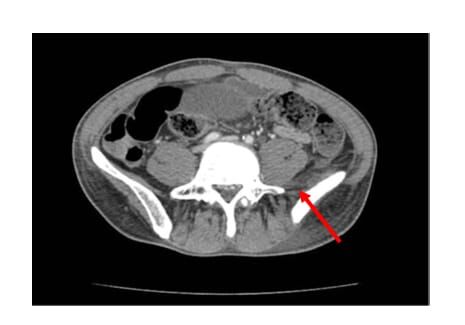

Kontrastlı abdominal ve pelvik bilgisayarlı tomografide, sol uyluk adduktor kaslarından başlayarak iliopsoas ve iliakus kaslarına uzanan, çok loküle, rim tutulumlu apse koleksiyonu izlendi. Bulgular iliopsoas apsesi ile uyumluydu.